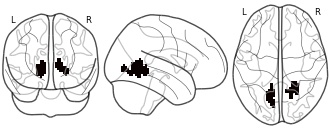

"name": "VBM_HeterogeneityMap",

"description": "Abnormal gray matter in BPD. Brain regions with significant heterogeneity (i.e. between-study variance) in the comparison of patients with BPD and healthy controls. Results are thresholded at at p<.005 & k>20. Note: Results are based on meta-analysis of group comparisons. Note2: Results were updated (see Erratum for this publication)",

"add_date": "2016-01-21T18:23:32.131003+01:00",